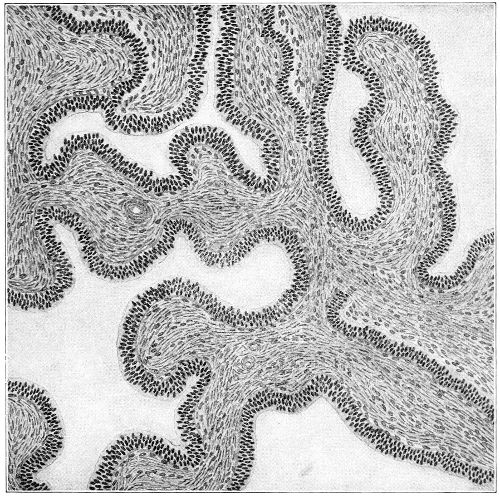

Several varieties of acute vaginitis may be recognized—the simple, the granular, the senile, and the emphysematous. It is unusual to find the entire surface of the vagina involved. The disease is confined to areas or patches separated by healthy tissue.

In granular vaginitis, which is the variety usually seen, the papillæ are infiltrated with small cells, and are much enlarged, so that the inflamed surface has a granular appearance.

Acute vaginitis is accompanied by dull pain and a sense of fulness in the pelvis. The discomfort is increased by standing, walking, defecation, and urination. There is a free discharge of serum or pus, which may be tinged with blood. The character of the discharge depends upon the variety and the period of the disease. Inspection, which can best be made through the Sims speculum, with the woman in the Sims or knee-chest position, shows the characteristic lesions of inflammation of the mucous membrane.